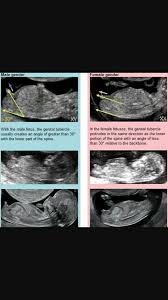

If it is moving upward then it is more likely a boy. Ultrasounds may reveal sex organs by 14 weeks but they aren t considered fully accurate until 18 weeks. Nipt results must be confirmed by a diagnostic test such as cvs or amniocentesis. However this service costs around 200 so isn t an option for everyone.

It reported a lower accuracy rate before 12 weeks gestation but concluded 3d ultrasound is a highly accurate and reproducible tool for fetal gender assignment prior to 14 weeks of gestation another study looked at 496 patients between 11 and 13 weeks plus six days pregnant who requested gender information during their first trimester screening. The 12 week ultrasound is the first chance to get a peek at your baby s sex organs and maybe some idea of what gender your baby is but at 12 weeks it s by no means guaranteed accurate. Getty contributor the nub theory. Nipt is a method of testing for the likelihood of genetic abnormalities in the first trimester.The gender of your baby is revealed at your second scan between 18 and 21 weeks but there s another test people use to determine if it s a boy or girl credit. Even then some mums argue that your child s gender isn t official until your child tells you their gender. The nub theory claims to be a lot more accurate than some of those old wives tales and claims you can even tell the sex of your baby just by looking at your 12 week ultrasound picture. Often be seen by weeks 18 to 20 the presence of male genitalia including testicles scrotum and penis is the irrefutable sign of male gender.